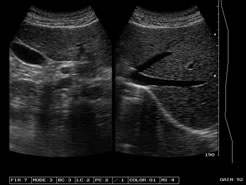

探頭:R6080陣元、3. 5MHz寬頻電子凸陣探頭,自動識別;

變頻:2.5MHz/3.OMHz/3.5MHz/4.0MHz/5.OMHz五種變頻可選;

圖像處理:可變孔徑,動態(tài)變跡、動態(tài)濾波、勾邊增強、數(shù)字時空濾波、8種γ校正、64種以上體位標記、行相關(guān)、幀相關(guān)、點相關(guān)、線性內(nèi)插等;

增益控制:8段TGC、GAIN調(diào)節(jié),總增益連續(xù)可調(diào);